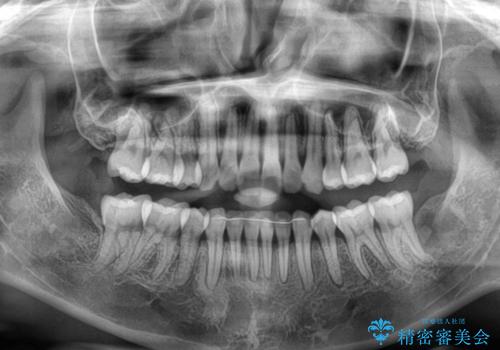

1. 抜歯矯正の軽度後戻りを解消 インビザライン矯正の治療前